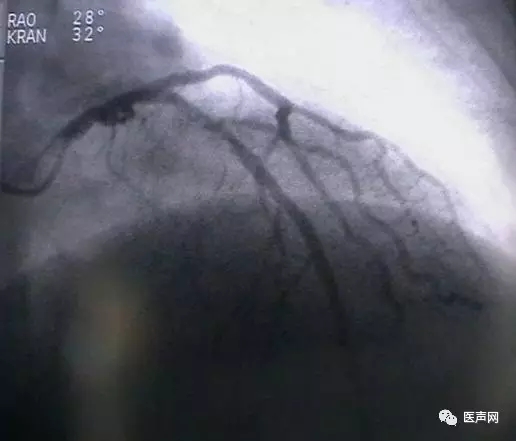

病例4:LAD PCI术后,对角支远端病变

此病变上次PCI不成功,因为LAD有支架,导丝穿过支架网眼入对角支有困难(对角支发出角度很大,成直角(箭头所示)。此次不再尝试,要学会放弃。

见下图: